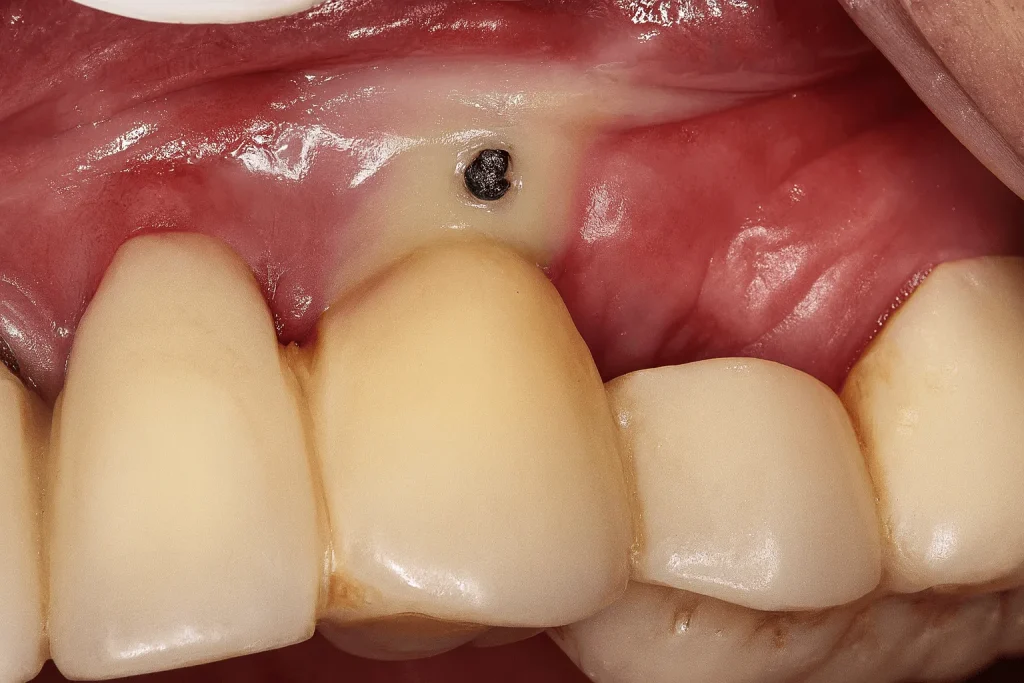

4. شل شدن پیچ اباتمنت یا روکش

یکی از علتهای آبسه بعد از ایمپلنت، شل شدن پیچ ایمپلنت یا اباتمنت است. زمانی که اباتمنت شل شود، بین ایمپلنت و روکش فاصله میافتد. فاصله ایجاد شده هم به جایی مناسب برای رشد باکتری تبدیل میشود. جالب است بدانیم که این فاصله را نمیتوان با هیچ ابزار معمولی مانند مسواک، تمیز کرد. این موضوع ممکن است سالها بعد از کاشت ایمپلنت رخ دهد.

- بررسی شل بودن اباتمنت یا روکش

- بررسی رابطه لثه با اباتمنت